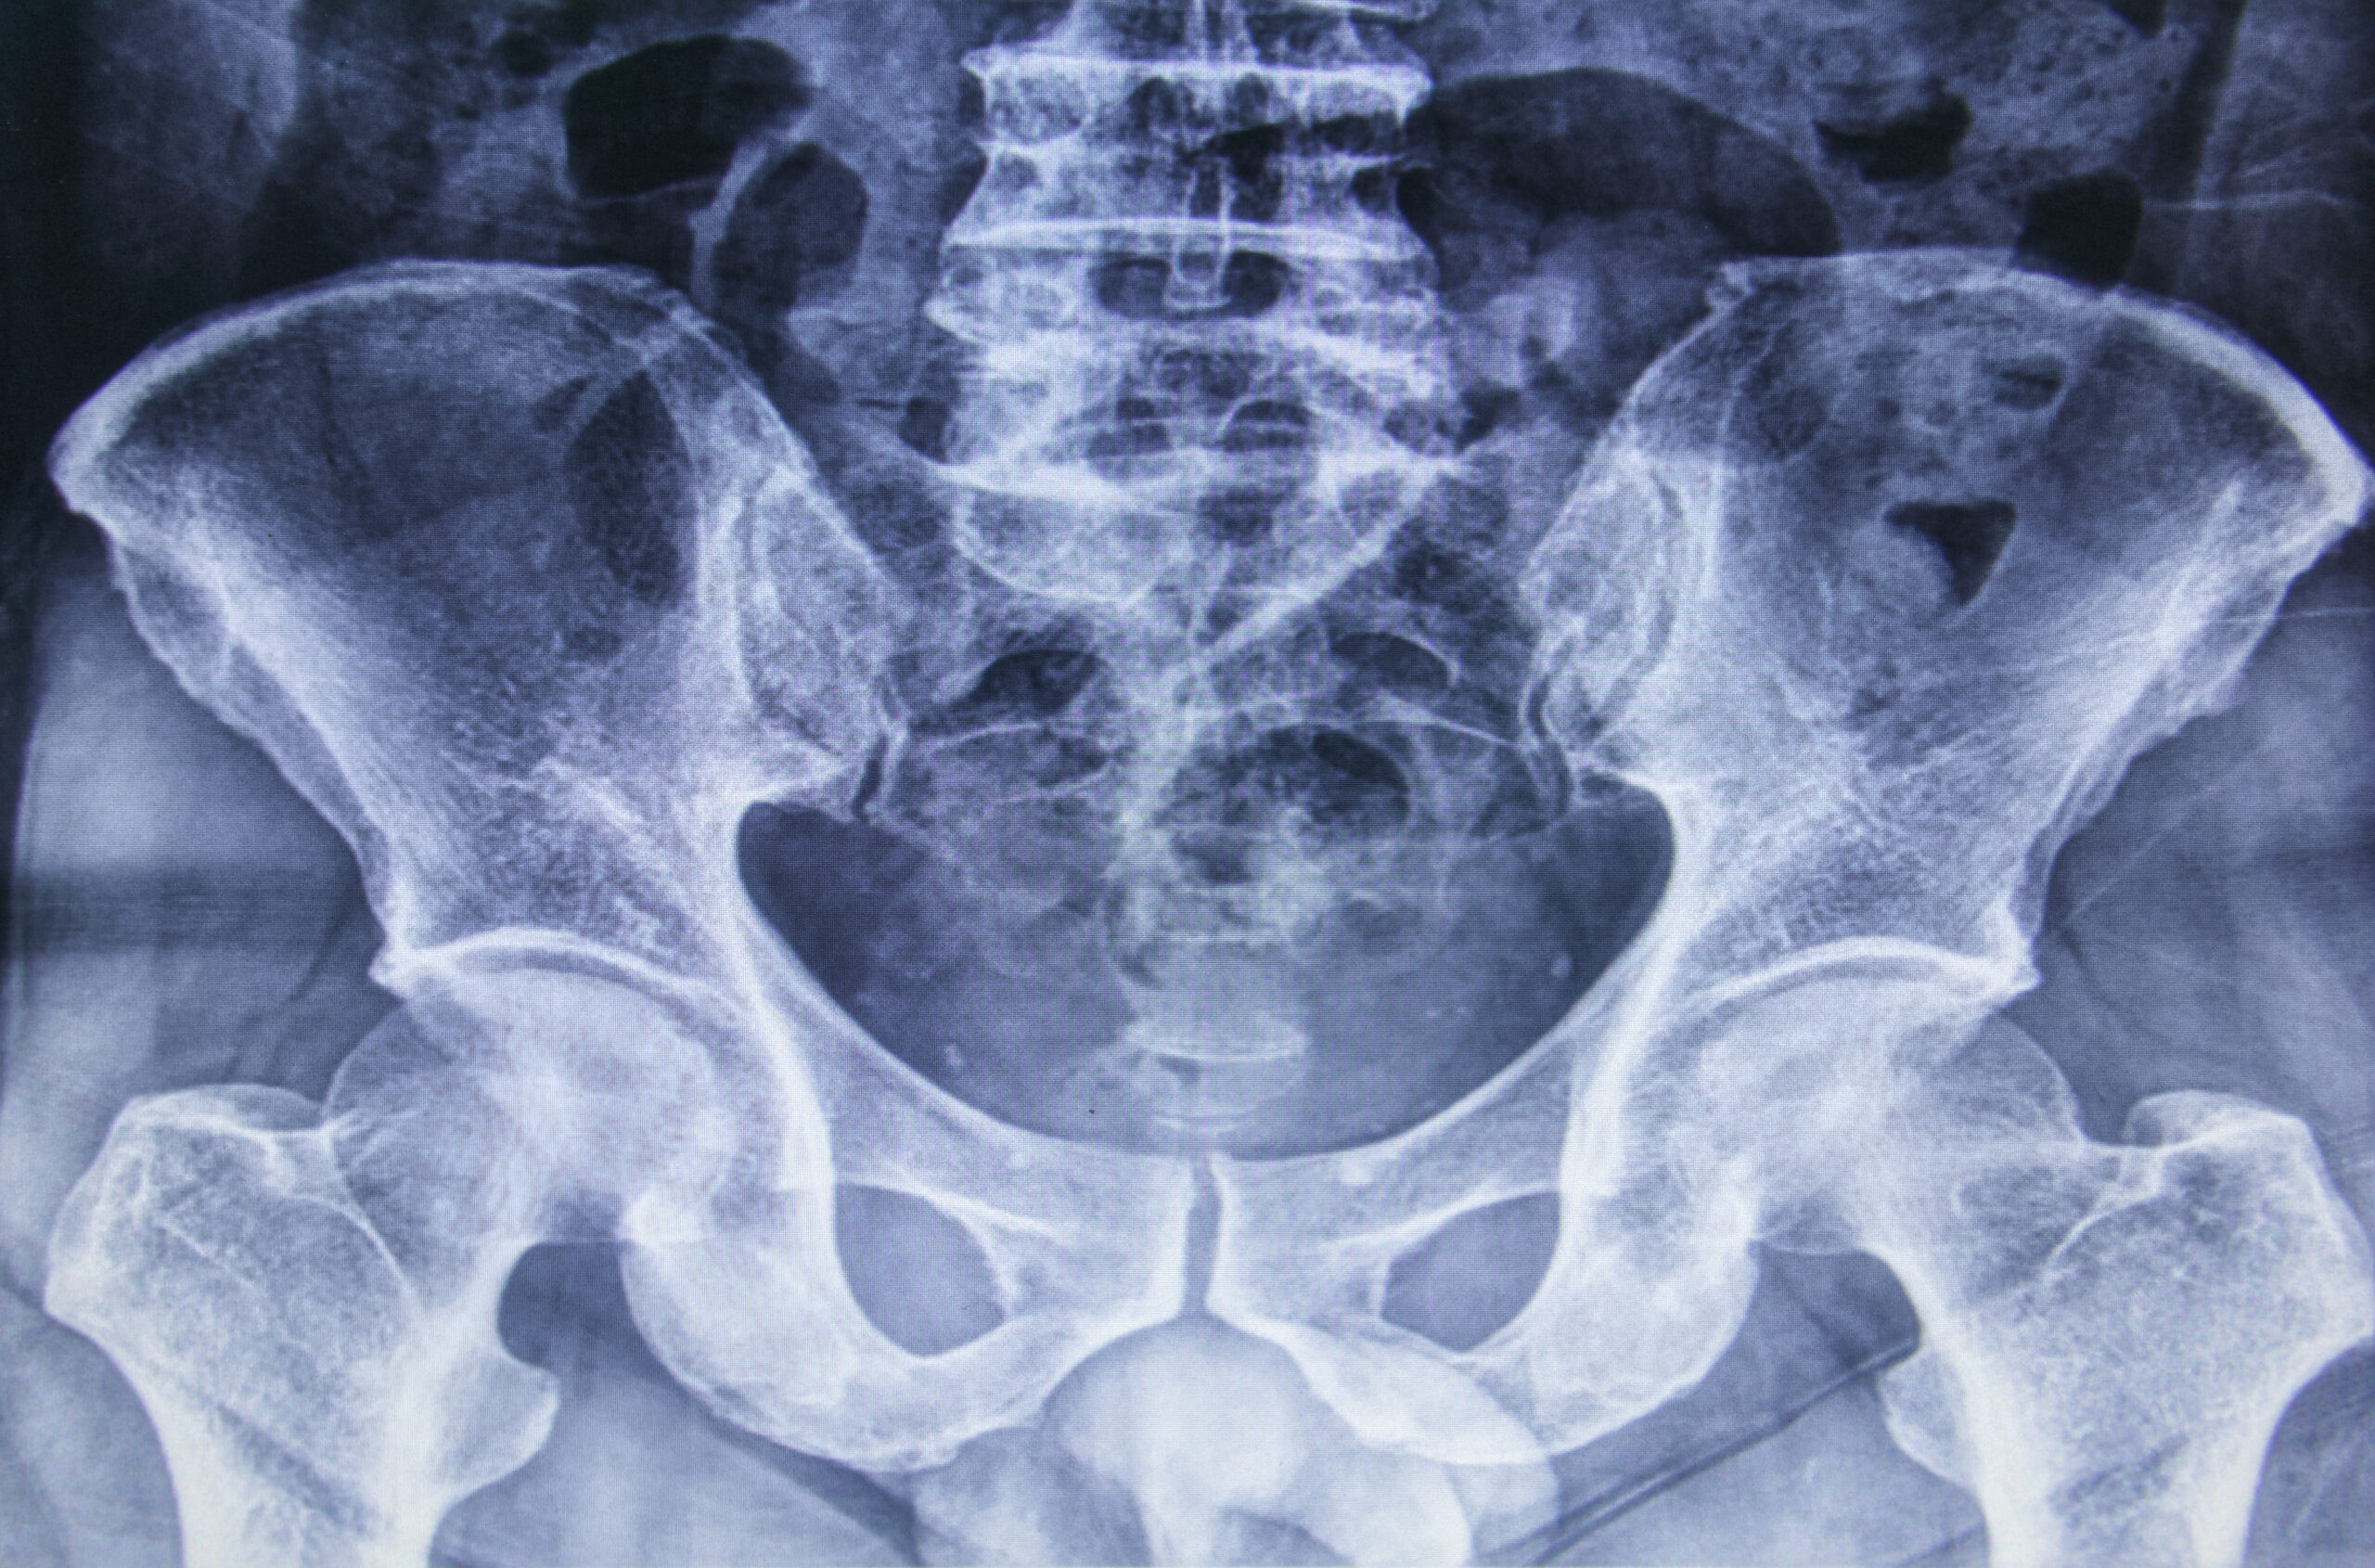

Is There An Alternative To A Hip Replacement . Hip replacement may be the only option for people with. Orthopedic surgeons are employing a new alternative to total hip replacement where a damaged hip is strengthened by injecting a. But there are an increasing number of alternatives to hip and shoulder replacement as well. Hip replacement surgery is a common procedure that is necessary when the hip joint is worn or damaged. But what if the joint. Common alternatives to a hip replacement. Sierra m.d., and his colleague, aaron krych, m.d., are among a few orthopedic surgeons in the united states to perform a regenerative surgery called fresh osteochondral allograft transplantation surgery (oats) to the femoral head as an alternative for hip replacement in select patients with avascular necrosis. But what if the joint. Hip replacement surgery is a common procedure that is necessary when the hip joint is worn or damaged. There are other treatments you can try first before having a hip replacement.